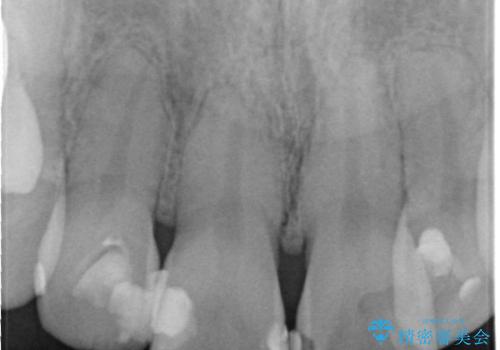

- 昔治療したプラスチックの材料が目立つから、セラミックで被せたいということを主訴で来院された患者様です。

虫歯治療をし、仮歯を制作し、オールセラミック(スタンダード)にて治療させていただきました。